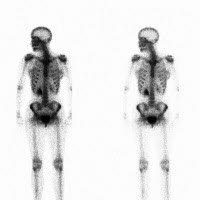

Scintigrafi av skjelettet: Hvor god er undersøkelsen?

Testen er bedre til å fange opp forandringer i skjelettet hos barn enn hos voksne. Tidlig beinsykdom og tilheling påvises ved skjelettscintigrafi lenge før de er synlige på røntgen. Ved osteomyelitt kan forandringer påvises allerede etter 2-3 dager, mens det kan ta 10-14 dager før røntgen viser forandringer. Testen er følsom (sensitiv) og viser sykelige forandringer, men den er lite spesifikk og kan ofte ikke gi svar på hva som er galt. Det vil da være nødvendig med andre undersøkelser som røntgen, CT, MR eller PET.